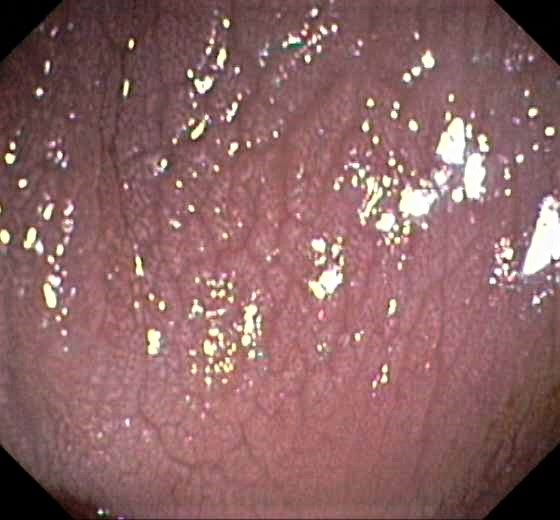

Chicken Skin Mucosa

Slight Mucosal Changes are frequently seen adjacent to a colorectal cancer or adenoma. First described by Shatz BA et al, they are called Chicken Skin Mucosa (CMS), and are supposed to occur as a result of fat accumulation in macrophages in the lamina propria adjacent to colonic neoplasms. In a series of 852 consecutive colonoscopies CMS was found adjacent to eight of 10 distal colorectal cancers, one of four of proximal colon cancers and 16 of 42 distal adenomas.